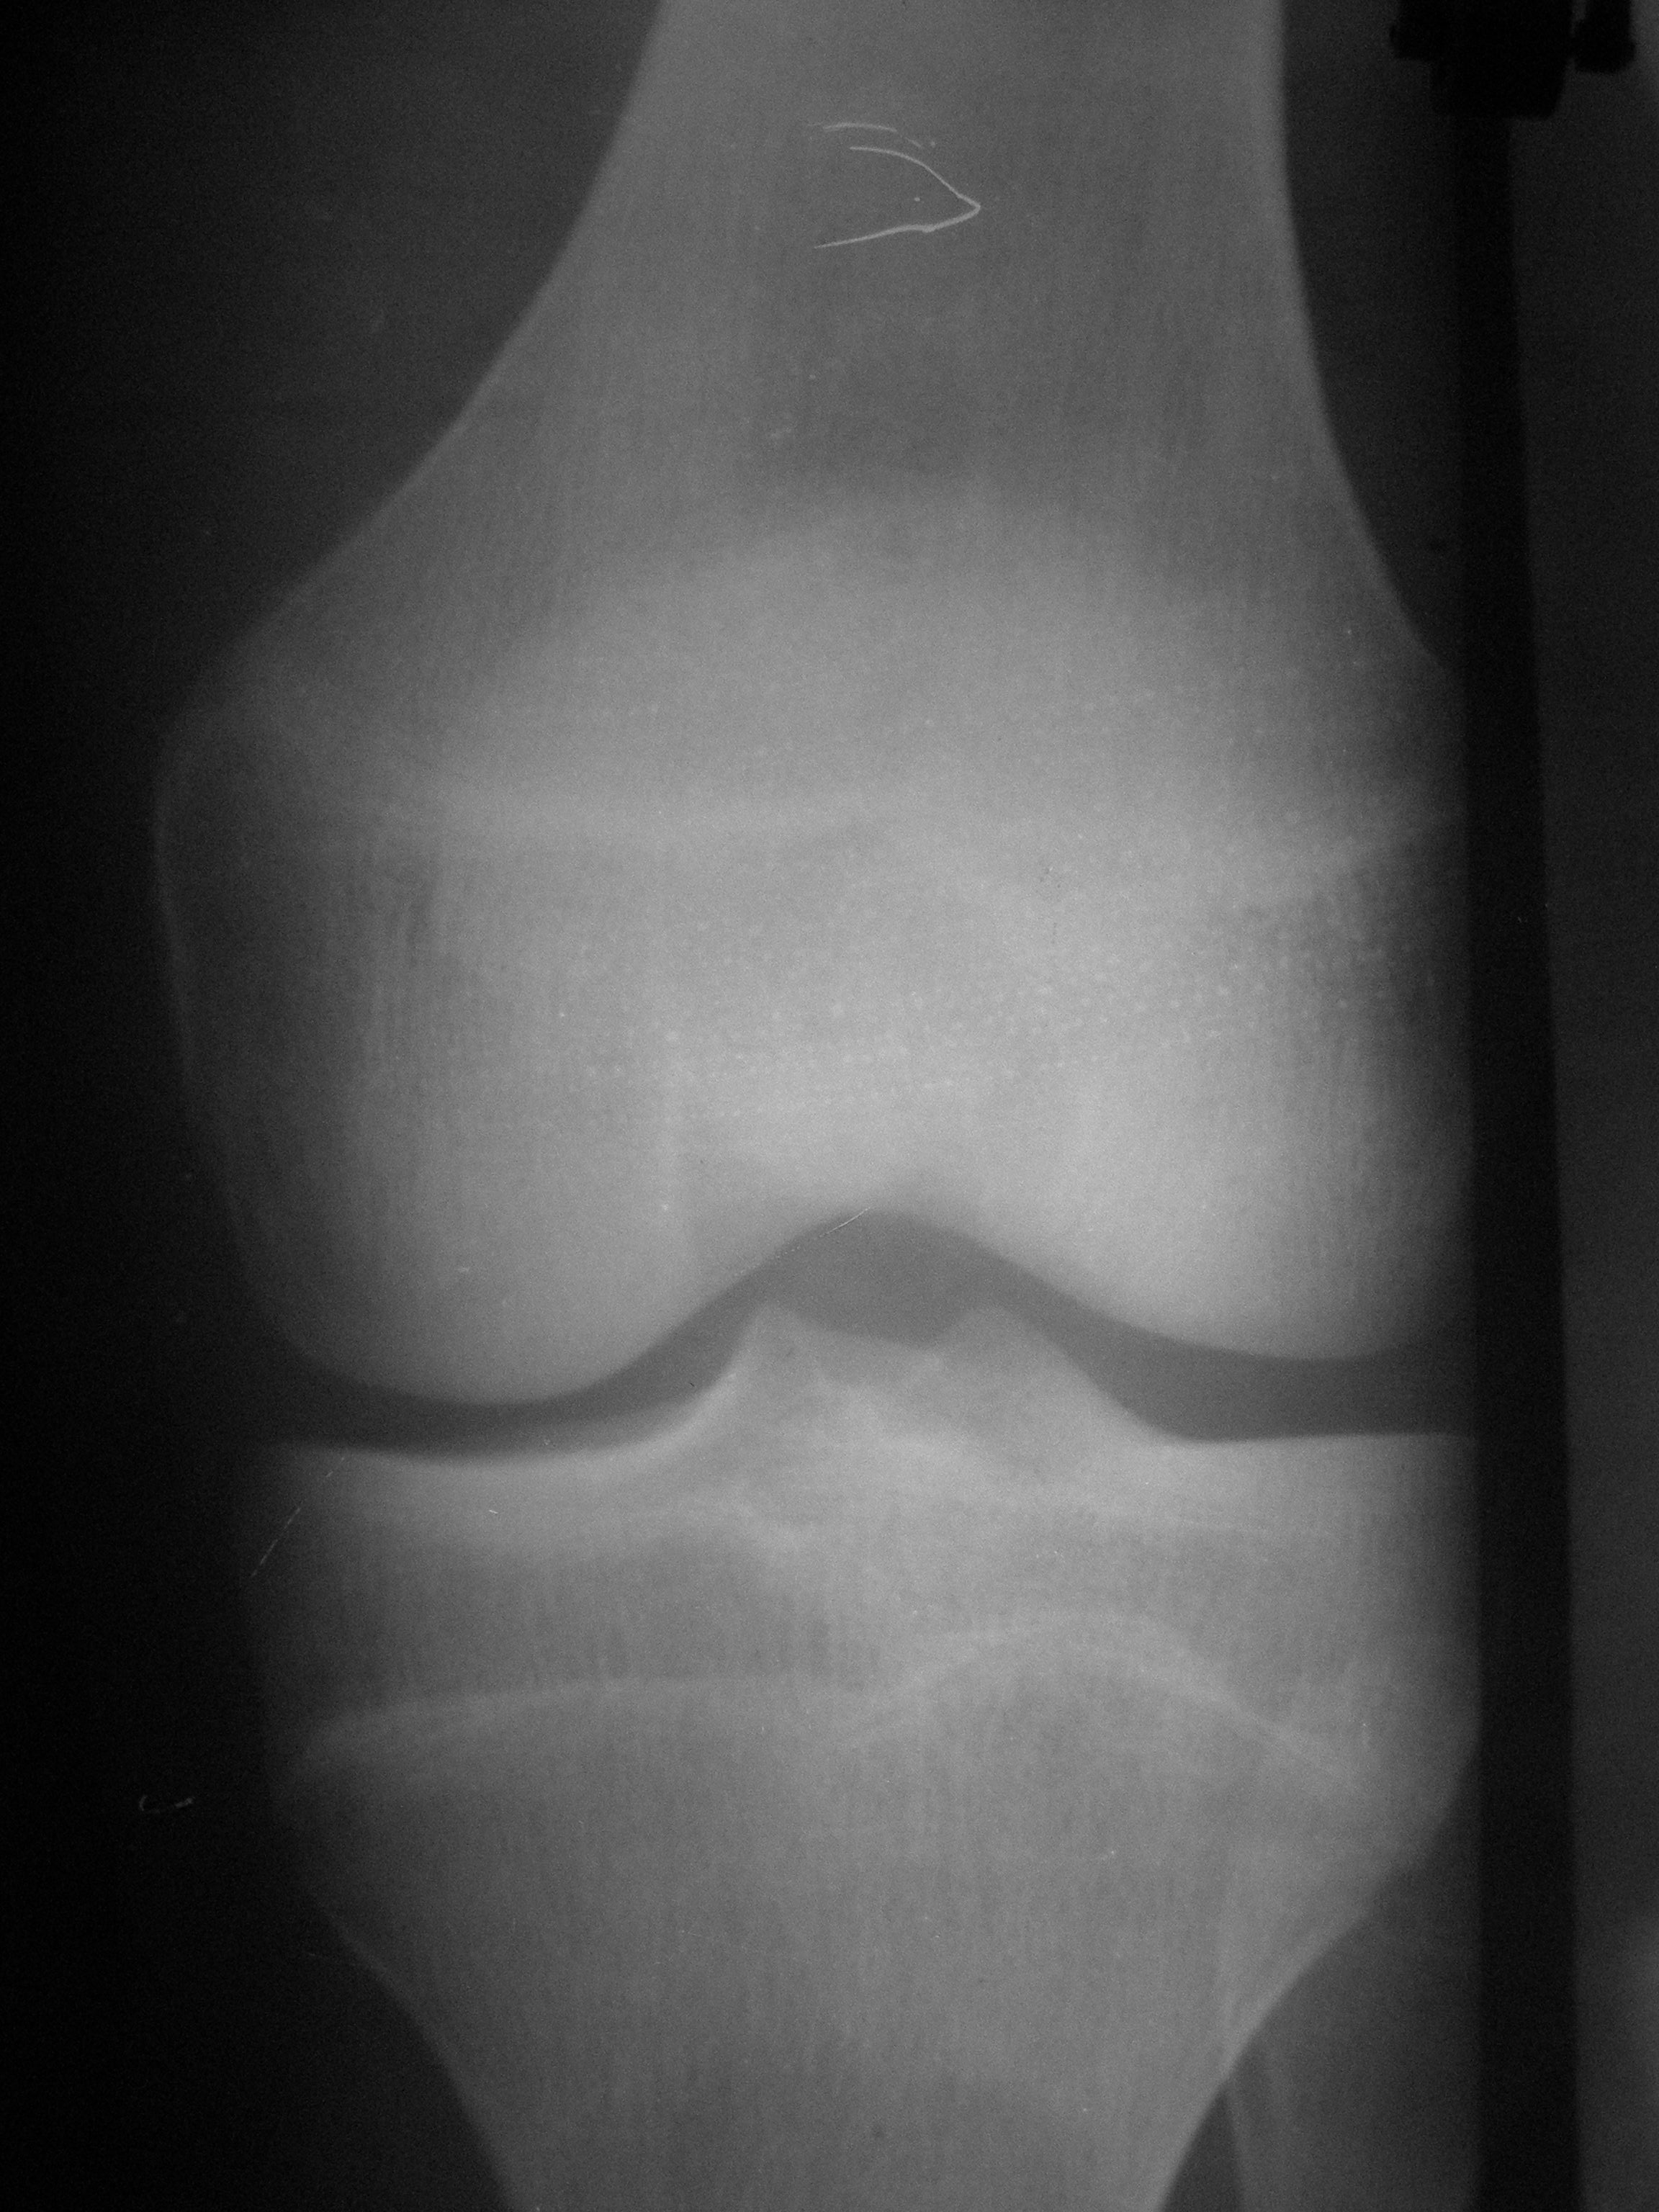

М.15лет. Жалобы на периодическую жгучую боль в L коленном суставе,после умеренной нагрузки, беспокоит 1мес. https://radiomed.ru/sites/default/files/styles/case_slider_image/public/user/15746/p4090030.jpg?itok=kvBtdL0b https://radiomed.ru/sites/default/files/styles/case_slider_image/public/user/15746/p4090031.jpg?itok=wUf85A5t ID:50918 Mon, 09/04/2012 - 17:48 #1 nelly Offline Last seen: 11 years 3 months ago Joined: 11.07.2011 - 19:19 Posts: 328 мне видится какой-то участок разряжения костной ткани в н3 диафиза БК..,не знаю как стрелочки ставить,а то отметила бы,а суставе артроз похоже имеется Mon, 09/04/2012 - 19:51 #2 ДокRg Offline Last seen: 12 years 6 months ago Joined: 30.03.2011 - 20:05 Posts: 105 nelly wrote: мне видится какой-то участок разряжения костной ткани в н3 диафиза БК..,не знаю как стрелочки ставить,а то отметила бы,а суставе артроз похоже имеется Я бы назвал этот участок разряжения - пятном Лудлофа( норма). А вот для исключения болезни Осгуд-Шляттера сделал бы снимки б/берцовых костей обеих ног с большим захватом. Mon, 09/04/2012 - 20:40 #3 maker4ik Offline Last seen: 8 years 9 months ago Joined: 19.10.2011 - 17:49 Posts: 2682 ДокRg wrote: nelly wrote: мне видится какой-то участок разряжения костной ткани в н3 диафиза БК..,не знаю как стрелочки ставить,а то отметила бы,а суставе артроз похоже имеется Я бы назвал этот участок разряжения - пятном Лудлофа( норма). А вот для исключения болезни Осгуд-Шляттера сделал бы снимки б/берцовых костей обеих ног с большим захватом. Пятно Лудлофа в эпифизе находится, а nelly про н/3 диафиза говорит. Mon, 09/04/2012 - 20:56 #4 Любовь С. Offline Last seen: 9 years 8 months ago Joined: 23.12.2010 - 01:58 Posts: 2324 Переснять диафиз в 2 проекциях. "Предоставляя весь смысл и совершенство в распоряжение одного только Бога, вы избавляете себя от бездны хлопот." Джон Уитборн. Mon, 09/04/2012 - 21:00 #5 nelly Offline Last seen: 11 years 3 months ago Joined: 11.07.2011 - 19:19 Posts: 328 да,да,я именно про это пятно,которое maker4ik указал стрелкой. Mon, 09/04/2012 - 21:17 #6 И.Бондаренко Offline Last seen: 17 hours 14 min ago Joined: 13.09.2011 - 22:55 Posts: 9209 Есть незначительное снижение медиальной суставной щели. А так бы написал норму. Tue, 10/04/2012 - 03:23 #7 Демчев Валентин... Offline Last seen: 7 years 10 months ago Joined: 08.02.2011 - 15:40 Posts: 445 Никакой болезни Осгуда-Шлаттера здесь нет. Переснять диафиз в 2-х проекциях, опять какой- нибудь метафизарный корковый дефект.

мне видится какой-то участок разряжения костной ткани в н3 диафиза БК..,не знаю как стрелочки ставить,а то отметила бы,а суставе артроз похоже имеется

Есть незначительное снижение медиальной суставной щели. А так бы написал норму.

Никакой болезни Осгуда-Шлаттера здесь нет. Переснять диафиз в 2-х проекциях, опять какой- нибудь метафизарный корковый дефект.